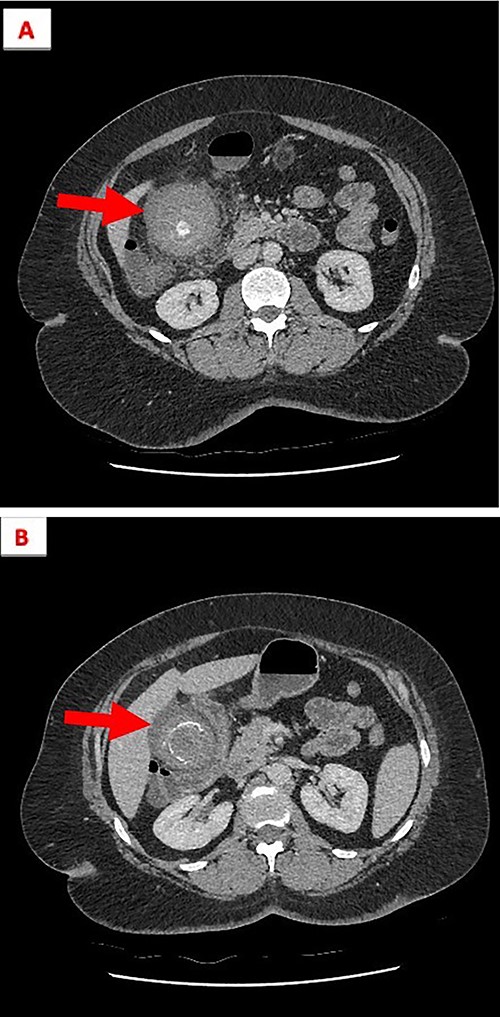

CT abdomen with intravenous contrast revealed a distended gall bladder containing numerous lamellate calculi and high-density fluid along with gall bladder wall thickness and pericholecystic fluid compatible with acute haemorrhagic calculus cholecystitis (see Figs 1 and 2).

(A) The gallbladder contains numerous lamellated calculi and is distended with high-density fluid. (B) Gall bladder wall thickening and high-density fluid, both features are compatible with acute HC.